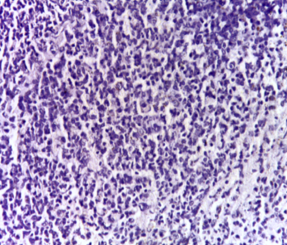

Immunohistochemical investigations

Immunohistochemical determination of the antibody specific for activated caspase-3 of the Control group showed negative results (fig. 1a) compared to the DMN group, as the activated caspase-3 was present in the cytoplasm of cells with morphology consistent with apoptosis (fig. 1b). While the groups injected with PRP and those administered orally with Qeurcetin showed negative results (fig. 1c and fig. 1d respectively).

Fig. 1(a-d): Immunohistochemical determination of the antibody specific for activated caspase-3 in splenic tissue, (a) Normal control showed a negative reaction, (b) DMN group showed a positive reaction, (c) PRP group showed negative reaction and (d) Qeurcetin group showed negative reaction (a-d X100)